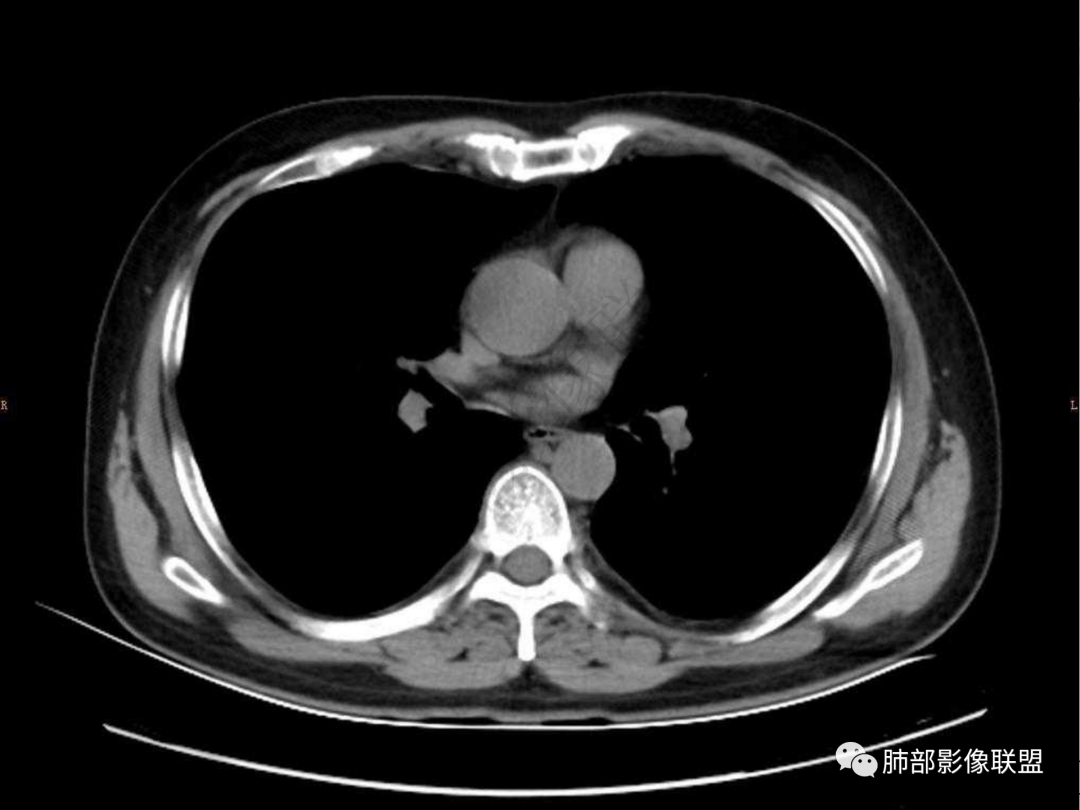

4.实性部分不均匀环形强化并显示一小范围低密度坏死区或空洞。较之肺窗,整体纵隔窗范围较小,提示病灶并不十分密实。抑或为不同时段图像。

5.双肺门及纵隔未见增大淋巴结。未见胸腔积液。

肺脓肿:可宽基底与胸膜相连,附近胸膜增厚——炎性特点

肺脓肿:边界模糊不清,或者块影为类圆形,无明显分叶,边缘平直为主,刀切征——炎性特点三、病灶周围特点:肺脓肿:病灶非远端有片状GGO——炎性特点四、近端支气管阻塞:肺脓肿:常有引流支气管伴管壁增厚或者支气管沿洞壁走行。五:坏死壁:肺脓肿:大多壁厚,少数壁薄,没有壁结节,内壁清楚光整——炎性特点

肺脓肿:环形强化,强化较显著。如出现明显囊壁样强化甚至边缘“憩室”样突出,高度支持肺脓肿。